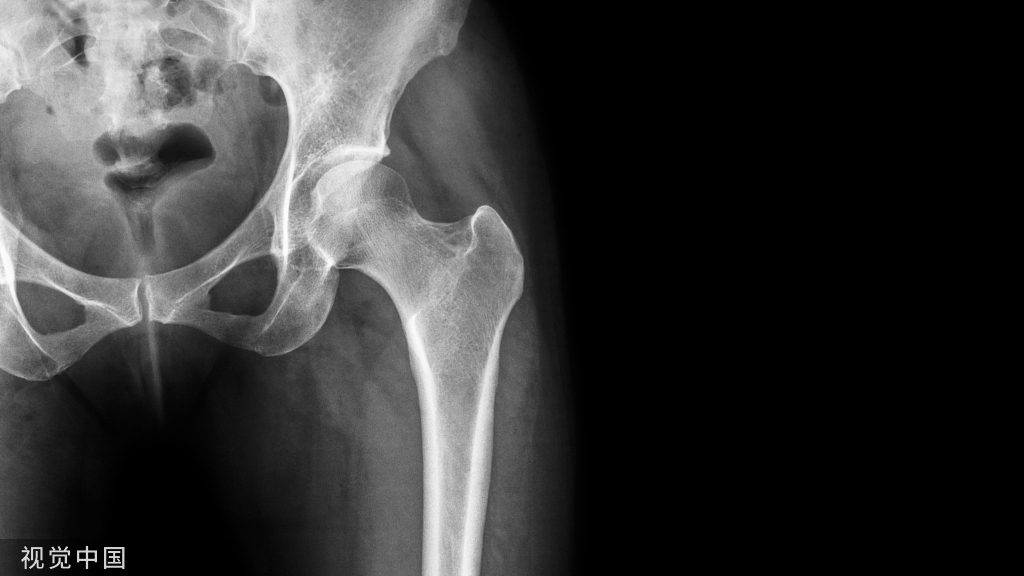

骨质疏松症是一种以骨量减少和骨组织微结构恶化为特征的系统性骨骼疾病,长期骨质流失导致骨强度受损和骨折风险增加,同时易伴发肌少症,多见于绝经后女性和老年男性,可分为原发性和继发性骨质疏松症.

骨质疏松症是一种以骨量减少和骨组织微结构恶化为特征的系统性骨骼疾病,长期骨质流失导致骨强度受损和骨折风险增加,同时易伴发肌少症,多见于绝经后女性和老年男性,可分为原发性和继发性骨质疏松症[1-2]。